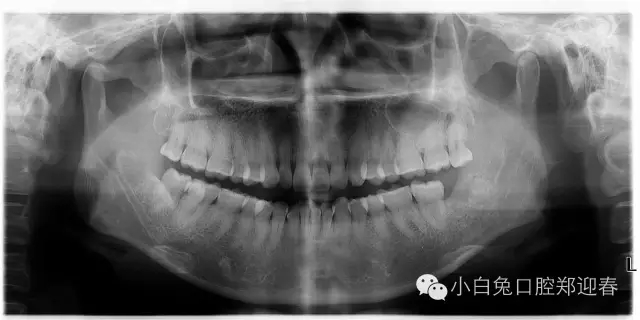

取出第一塊牙根部分,片子顯示依然存在遺留

一例智齒斷根進行二次拔除的感悟